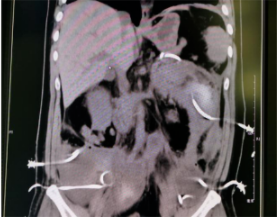

廣泛的腹膜后壞死合并感染